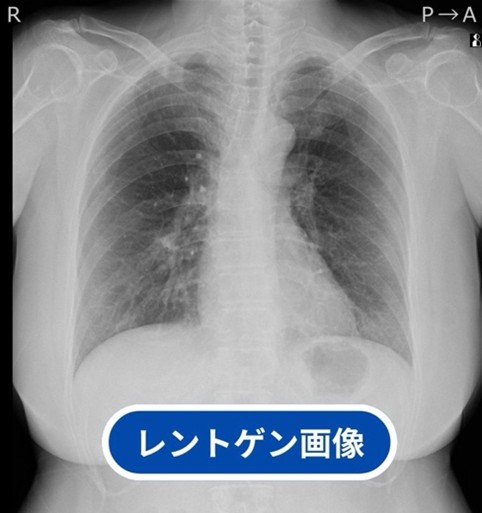

通常の胸部レントゲン検査と喀痰細胞診検査では早期のがんを発見するのは、なかなか難しいのが現状ですが、胸部CT検査では、肺がん発見率は、胸部レントゲン検査に比べて10倍程高いと言われており、肺がんの死亡率の低下に肺がんのCT検査が有効であるとされています。

レントゲン